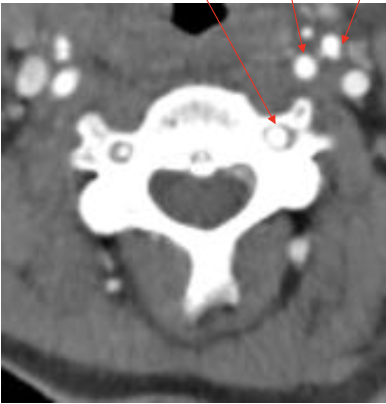

椎弓根

Pedicle

椎动脉

Vertebral artery

分叉棘突

Bifid Spinous process

前结节

Anterior tubercle

后结节

Posterior tubercle